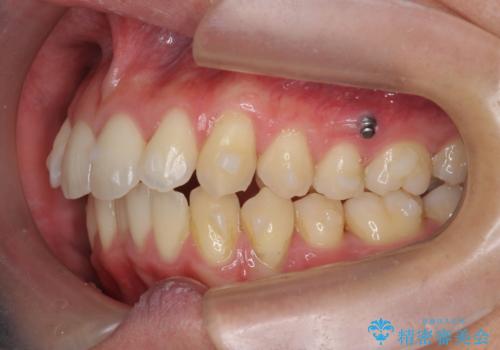

過蓋咬合・上顎前突・叢生を改善するマウスピース矯正

- 前歯のがたつき、不揃いさの改善を求めて来院されました。

・前歯の深い噛み合わせ (過蓋咬合)

・上顎前突(Angle Class2)

・叢生(がたつき)

以上のような問題点をマウスピース矯正インビザラインとマイクロインプラントを用いて矯正治療を行い改善して行きます。

20時間以上のマウスピース装着、ゴムかけを遵守していただいたおかげでしっかりと噛み合わせ、がたつきの改善を行うことができました。